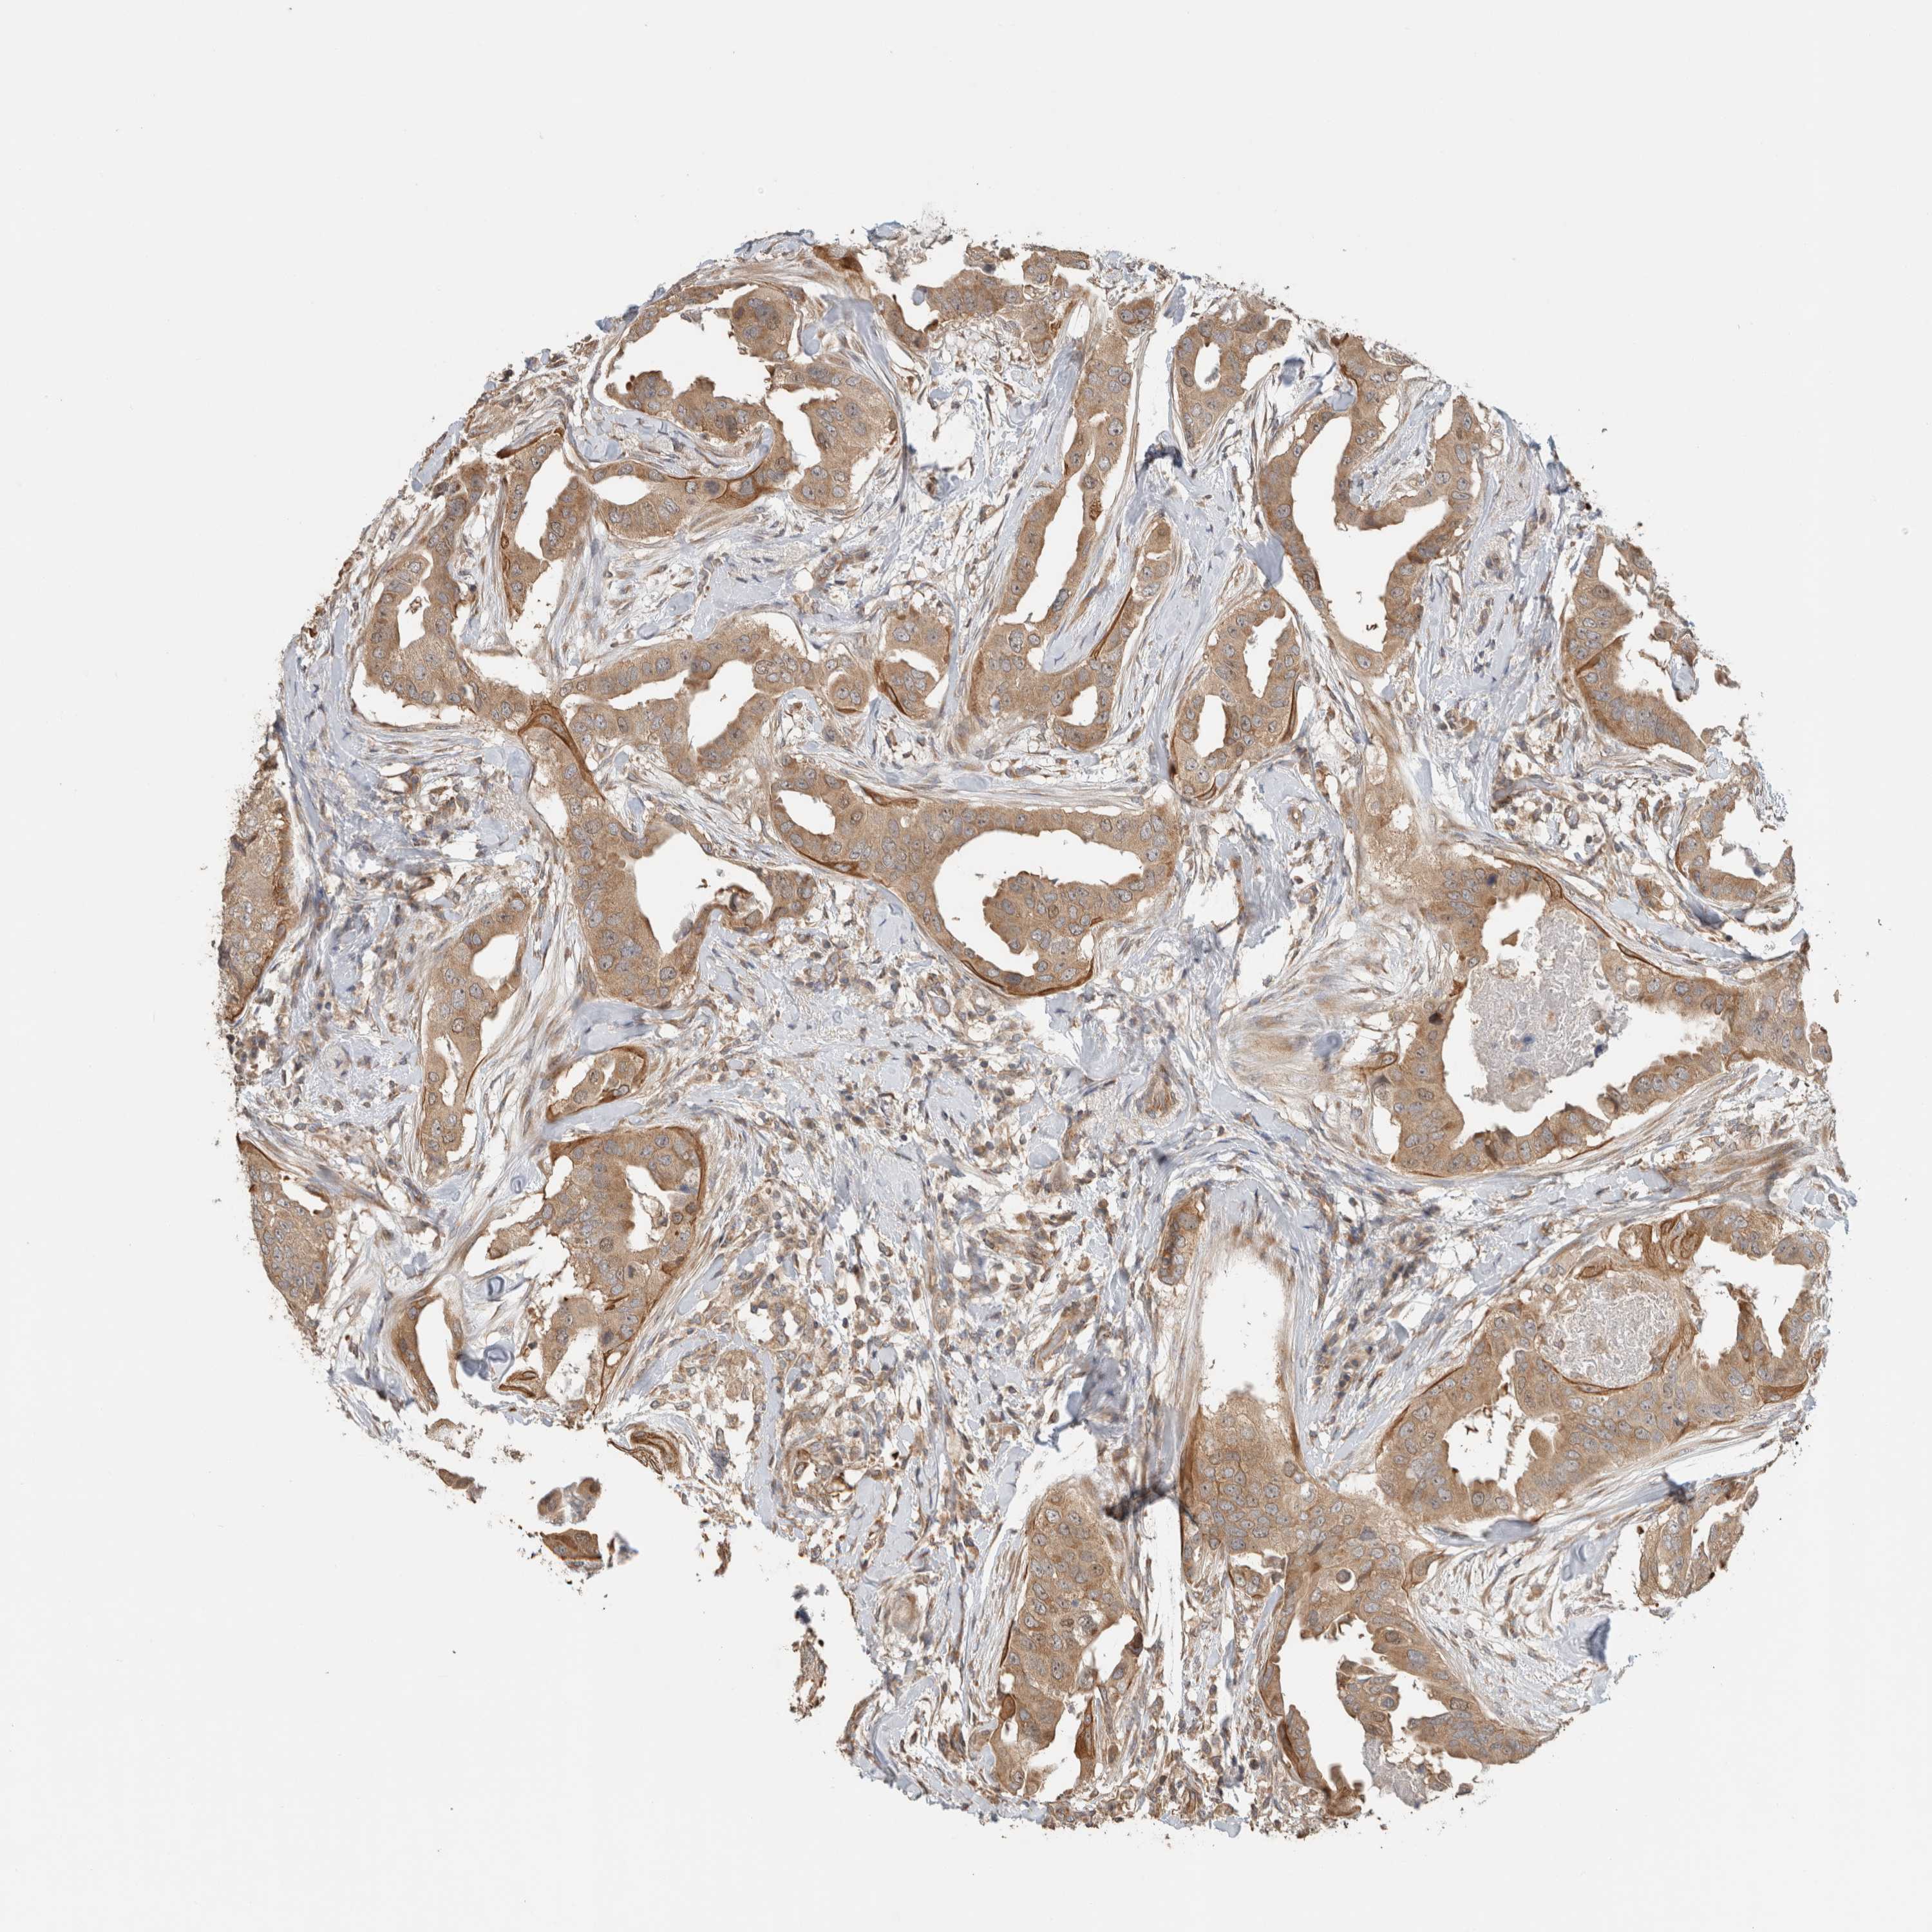

BRCA TCGA BRCA VALIDATION PROTEIN EXPRESSION